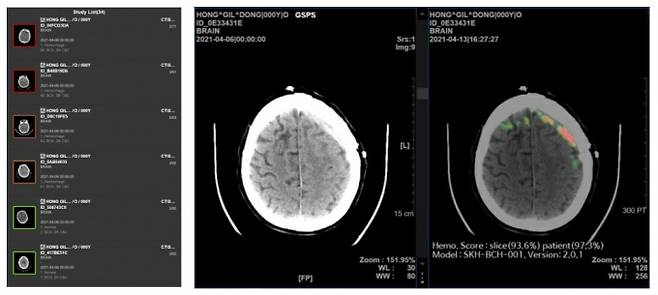

퍼플AI는 SK C&C의 AI 헬스케어팀과 서울대학교병원 및 아주대학교병원의 영상의학과 교수진이 공동 창업한 스타트업이다. 2019년 착수한 3개 기관의 공동 연구개발(R&D)을 통해 뇌출혈 AI, 뇌경색 AI, 뇌동맥류 AI 등 의료기기 솔루션 및 인허가를 확보했다. 전국 약 40개 종합병원에 적용해 임상 현장에서의 유효성도 입증한 바 있다.

대표 솔루션인 '메디컬 인사이트 플러스 뇌출혈'은 뇌 CT영상을 수초 내로 분석해 약 98%의 정확도로 출혈 위치와 이상 여부를 의료진에게 알려주는 서비스다. 뇌출혈은 발병 후 1달 이내 사망률이 35%~52%일 뿐만 아니라, 골든타임이 3시간에 불과한 중증·응급 질환이다.

다수의 임상 실증 연구에서 미세한 출혈도 신경두경부 영상의학전문의 수준으로 탐지해 의료진의 진단 정확도를 높이고 응급실 진료 시간을 단축한 효과를 보였다. 해당 연구 결과를 바탕으로 2024년 보건복지부 통합심사에서 혁신의료기술로 지정됐으며, 미국 식품의약국(FDA) 품목 허가도 취득했다.